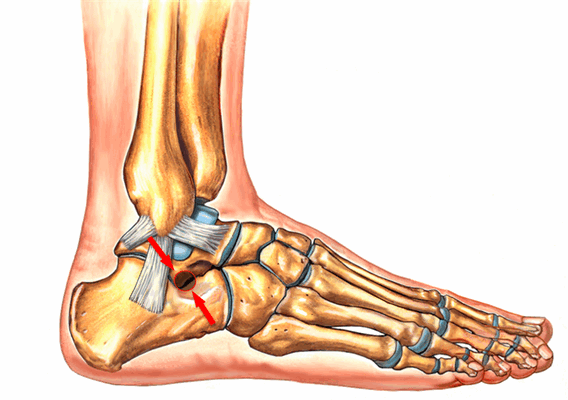

Поперечный сустав предплюсны или сустав Шопара состоит из таранно-ладьевидного и пяточно-кубовидного суставов. В обоих суставах есть фасетки овальной формы, ось которых проходит по наибольшему диаметру овала. В нейтральном положении стопы оси находятся под углом, а в положении пронации стопы оси становятся параллельными. В положении супинации угол между фасетками достигает максимума. Он больше, чем угол в нейтральном положении и чем угол в положении пронации. Головка таранной кости имеет выпуклую поверхность, а головка ладьевидной кости, которая сочленяется с ней, имеет, соответственно, вогнутую поверхность. Площадь фасетки таранной кости больше, чем площадь фасетки ладьевидной кости. В сагиттальной плоскости сустав Шопара расположен на расстоянии 32-36% от крайней точки пяточного бугра.

Рис. 1. Сустав Шопара с наружной и внутренней поверхности

Рис. 2. Сустав Шопара по тыльной поверхности стопы. Сустав включает в себя пяточно-кубовидный и таранно-ладьевидный суставы

Сустав Шопара укреплен несколькими связками. На тыльной поверхности сустава имеются 4 связки.

- Вилкообразная пяточно-ладьевидно-кубовидная связка состоит из двух частей - пяточно-ладьевидной и пяточно-кубовидной, которые расположены наподобие буквы V. Связка соединяет между собой пяточную, ладьевидную и кубовидную кости, имеет наибольшее значение для удержания этих костей и носит название «ключа» сустава.

- Тыльная пяточно-кубовидная связка расположена более дорзально, чем вилкообразная.

- Длинная пяточно-кубовидная связка расположена более поверхностно, идет от пяточной к кубовидной кости и своими поверхностными волокнами достигает латеральных плюсневых костей.

- Короткая пяточно-кубовидная связка представляет собой широкое образование, которое имеет длину 2 см.

На подошвенной поверхности есть 3 связки.

1. Пяточно-ладьевидная или прыжковая связка. Связка проходит по подошвенной и медиальной поверхности сустава и состоит из верхне-медиальной и нижней связок, которые образуют аппарат, поддерживающий таранную кость по подошвенной поверхности стопы. Связки противостоят смещению головки таранной кости в медиальном и подошвенном направлении, и, т.о. удерживают продольный свод стопы.

2. Верхне-медиальная связка. Пучки волокон перемежается с участками хряща. Эластические волокна отсутствуют. Верхне-медиальная связка вместе с ладьевидной костью и апофизом пяточной кости образует костно-гленоидальную полость. Это полость вогнутой формы, которая охватывает головку таранной кости. Во время физической нагрузки под давлением таранной кости полость деформируется. При этом связка не растягивается и сохраняет свою длину. Верхне-медиальная связка вплетается в дельтовидную связку голеностопного сустава. Вместе обе связки соединяются с сухожилием задней большеберцовой мышцы. Связки обладают практически одинаковыми механическими свойствами.

3. Нижняя связка. Нижняя связка расположена под верхне-медиальной связкой. Она растягивается под давлением со стороны таранной кости.

Рис. 3. Связки сустава Шопара:

TN - тыльная таранно-ладьевидная связка.

DDC - тыльная пяточно-кубовидная связка (Tafur M.)

В конструкции сустава Шопара имеются 2 опорные колонны. В состав медиальной колонны входят структуры, образующие таранно-ладьевидный сустав, в состав латеральной колонны - структуры, которые образуют пяточно-кубовидный сустав. Отдельные части сустава Шопара неравноценны с функциональной точки зрения. Для движения стопы в нескольких плоскостях таранно-ладьевидный сустав более важен, чем пяточно-кубовидный. Основное движение, которое происходит в таранно-ладьевидном и пяточно-кубовидном суставах - это ротация переднего отдела стопы относительно заднего отдела. Ротация осуществляется вокруг продольной оси, которая расположена в горизонтальной плоскости. Ротация лежит в основе инверсии и эверсии заднего отдела стопы и супинации-пронации всей стопы. Движение в суставе Шопара сопряжены с движением в голеностопном и подтаранном суставах. Разгибание стопы сочетается с эверсией и отведением, сгибание - с инверсией и приведением стопы. Суставы, которые входят в состав медиальной колонны, обладают разной подвижностью. В таранно-ладьевидном суставе сгибание и разгибание превышает подвижность в дистально расположенном ладьевидно-клиновидном суставе. В суставе Шопара происходит 1/5 всей амплитуды сгибания дистального отдела нижней конечности. Строение сустава Шопара позволяет сочетать движения в сагиттальной плоскости с ротацией стопы. Работа сустава Шопара дополняет функцию голеностопного и подтаранного сустава, делает стопу эластичной для прилегания к опоре и создает жесткий рычаг для отталкивания от неё.